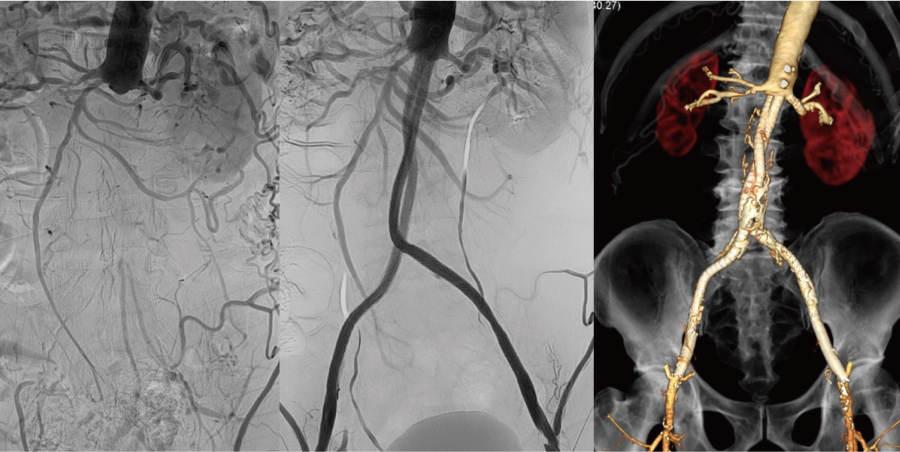

03

腹部大動脈から両下肢腸骨動脈の血管内を治療しました。治療翌日に自ら歩いて帰られました。